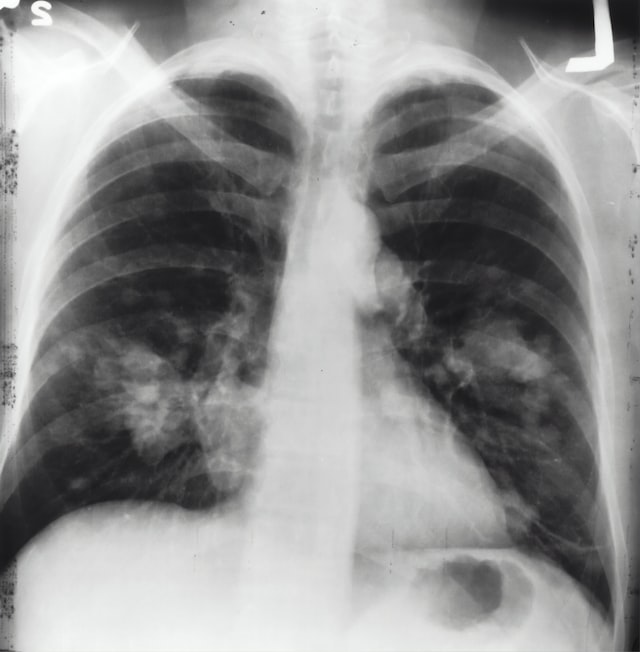

Xray of the lungs